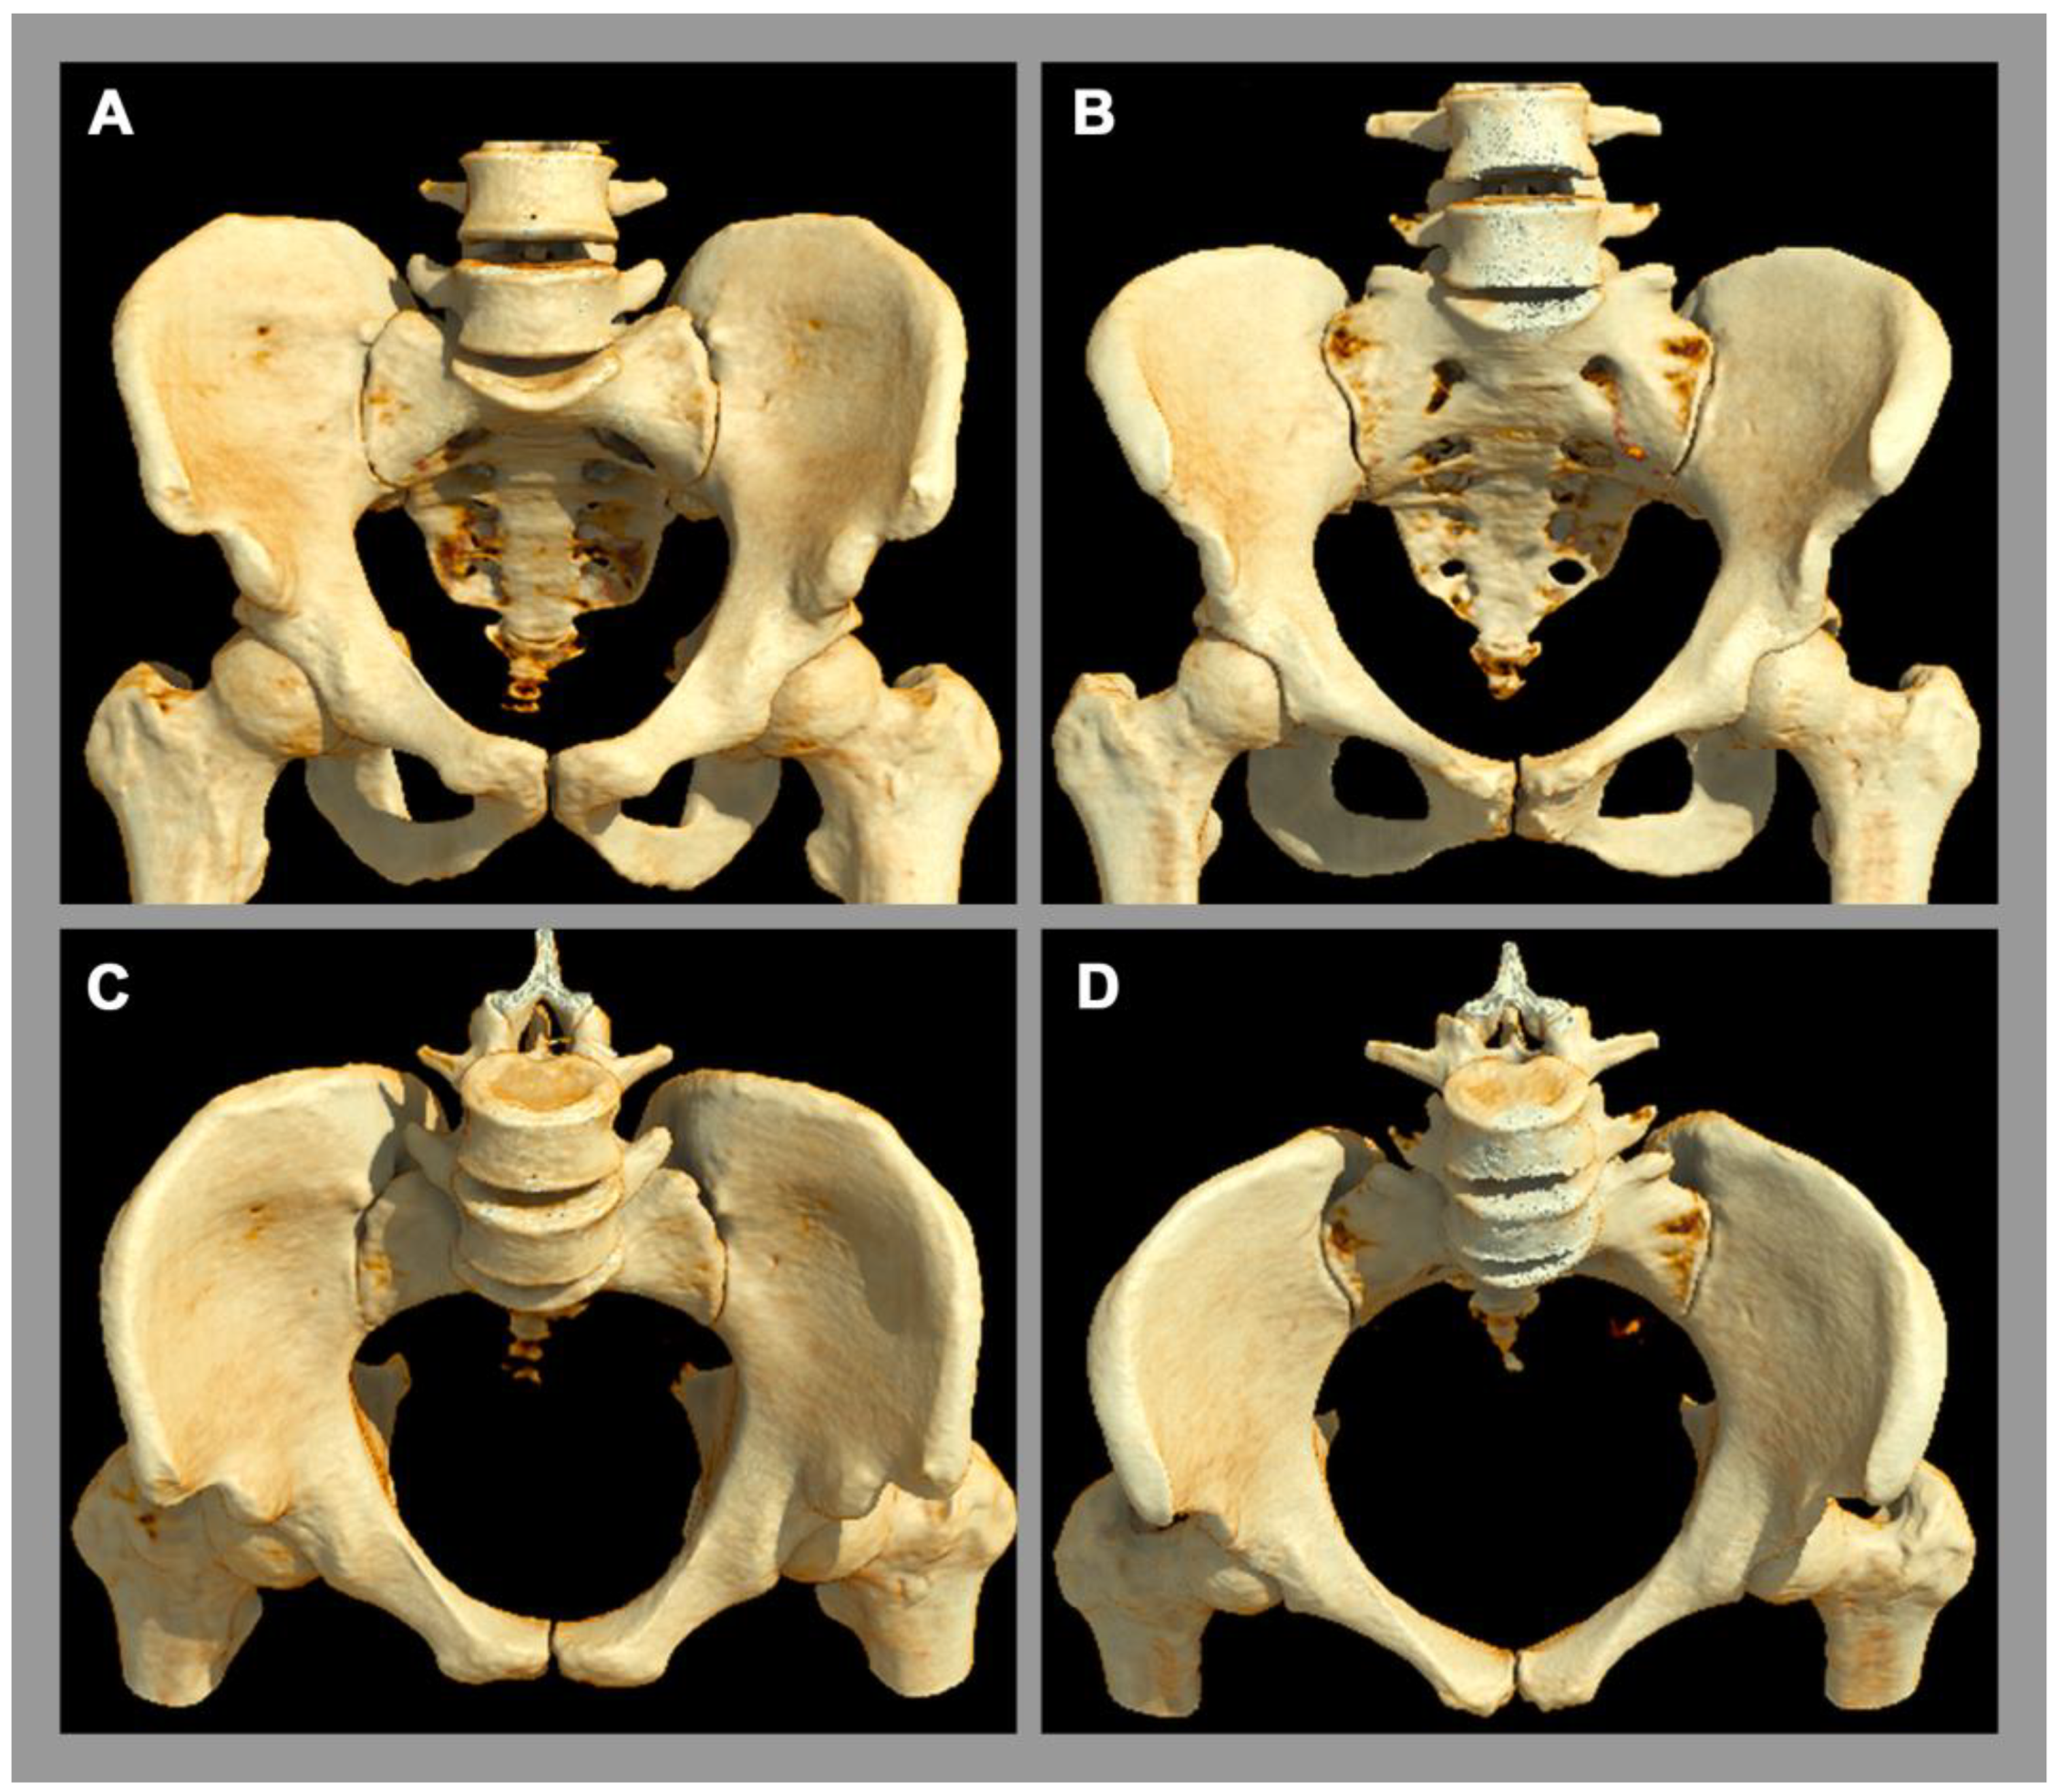

Osteitis condensans ilii is a frequent pathology of the SIJ [5], which is classified as a non-inflammatory disease. Its origin is attributed to mechanical stress and imbalance across the SIJ, e.g., during pregnancy and childbirth [2], causing a chronic stress response. Clinically, affected patients present with chronic back pain, which typically begins before the age of 45 [5]. Osteitis condensans ilii is significantly more common in women than in men, possibly due to the different biomechanical properties of the SIJ and flexible ligamentous structures in the female pelvis [5], especially concerning delivery. The typical imaging finding at the sacroiliac joint is sclerosis and its specific distribution pattern in the anterior and inferior part of the SIJ with a typical triangular shape (also called “hyperostosis triangularis ilii”) [5]. In addition, bone marrow edema can also be seen in osteitis condensans ilii, but this is not specific, since other factors, such as sporting activities, can also lead to bone marrow edema in the SIJ in the region of mechanical stress [54,55], see Figure 3.

Figure 3.

Sacroiliac joint load zones. 3D computed tomography reconstruction. (A,C) Lateral view of the ilium. (B,D) Lateral view of the sacrum. Male pelvis (A,B). Female pelvis (C,D). There are sex differences in the distribution of the load zone (red area) with respect to the rest of the joint surface (purple area). In women, the center of gravity is more ventrally located.

In the diagnostic process of degenerative conditions of the SIJ, naturally occurring aging should always be considered. These imaging lesions are to be regarded as a consequence of repetitive, inappropriate biomechanical stress, which is accompanied by joint wear and may result in lower back pain. Besides patchy small-sized focal spots of bone marrow edema, sclerosis, and osteophytes are typical findings, but their distribution pattern in the general population differ between the sexes: In men, the degenerative changes are mainly localized in the ventral part of the SIJ, whereas in women they are more likely to be found ventrally and dorsally [6,56]. In addition, a different age distribution is also evident, where degenerative changes in women show an early peak between 45 and 54 years of age, whereas, in men, a steady increase in degenerative lesions of SIJ with increasing age has been shown [6]. Furthermore, SIJ degeneration in imaging is associated with degenerative changes of the lumbar spine in men but not in women [57].